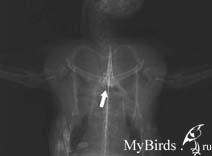

Фатальный вывих грудино-клювовидного сустава (art. Sternocoracoidea) сложно распознать при нормальной вентродорсальной рентгеноскопии. Когда крыло вытянуто, разделение клювовидного отростка и грудины практически незаметно.

Вывих art. Sternocoracoidea: смещение клювовидного отростка через среднюю линию не видно до тех пор, пока не проведено провокационное исследование (сведение крыльев по направлению к середине).